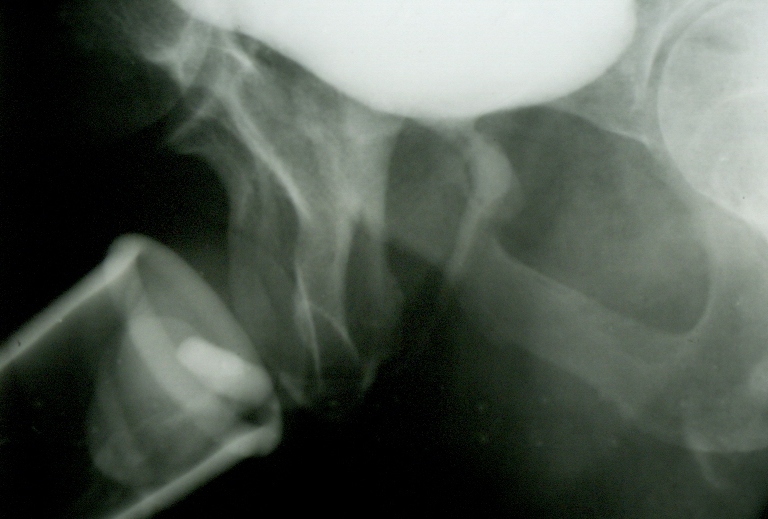

Normal serial radiographies taken during

urination show a funnel

enlargement (1,5 centimetre) of the

prostatic urethra

(B).

Serial radiographies taken during urination show

a narrowing

(3 millimetres) of the

when

prostate is fibrous

(C).